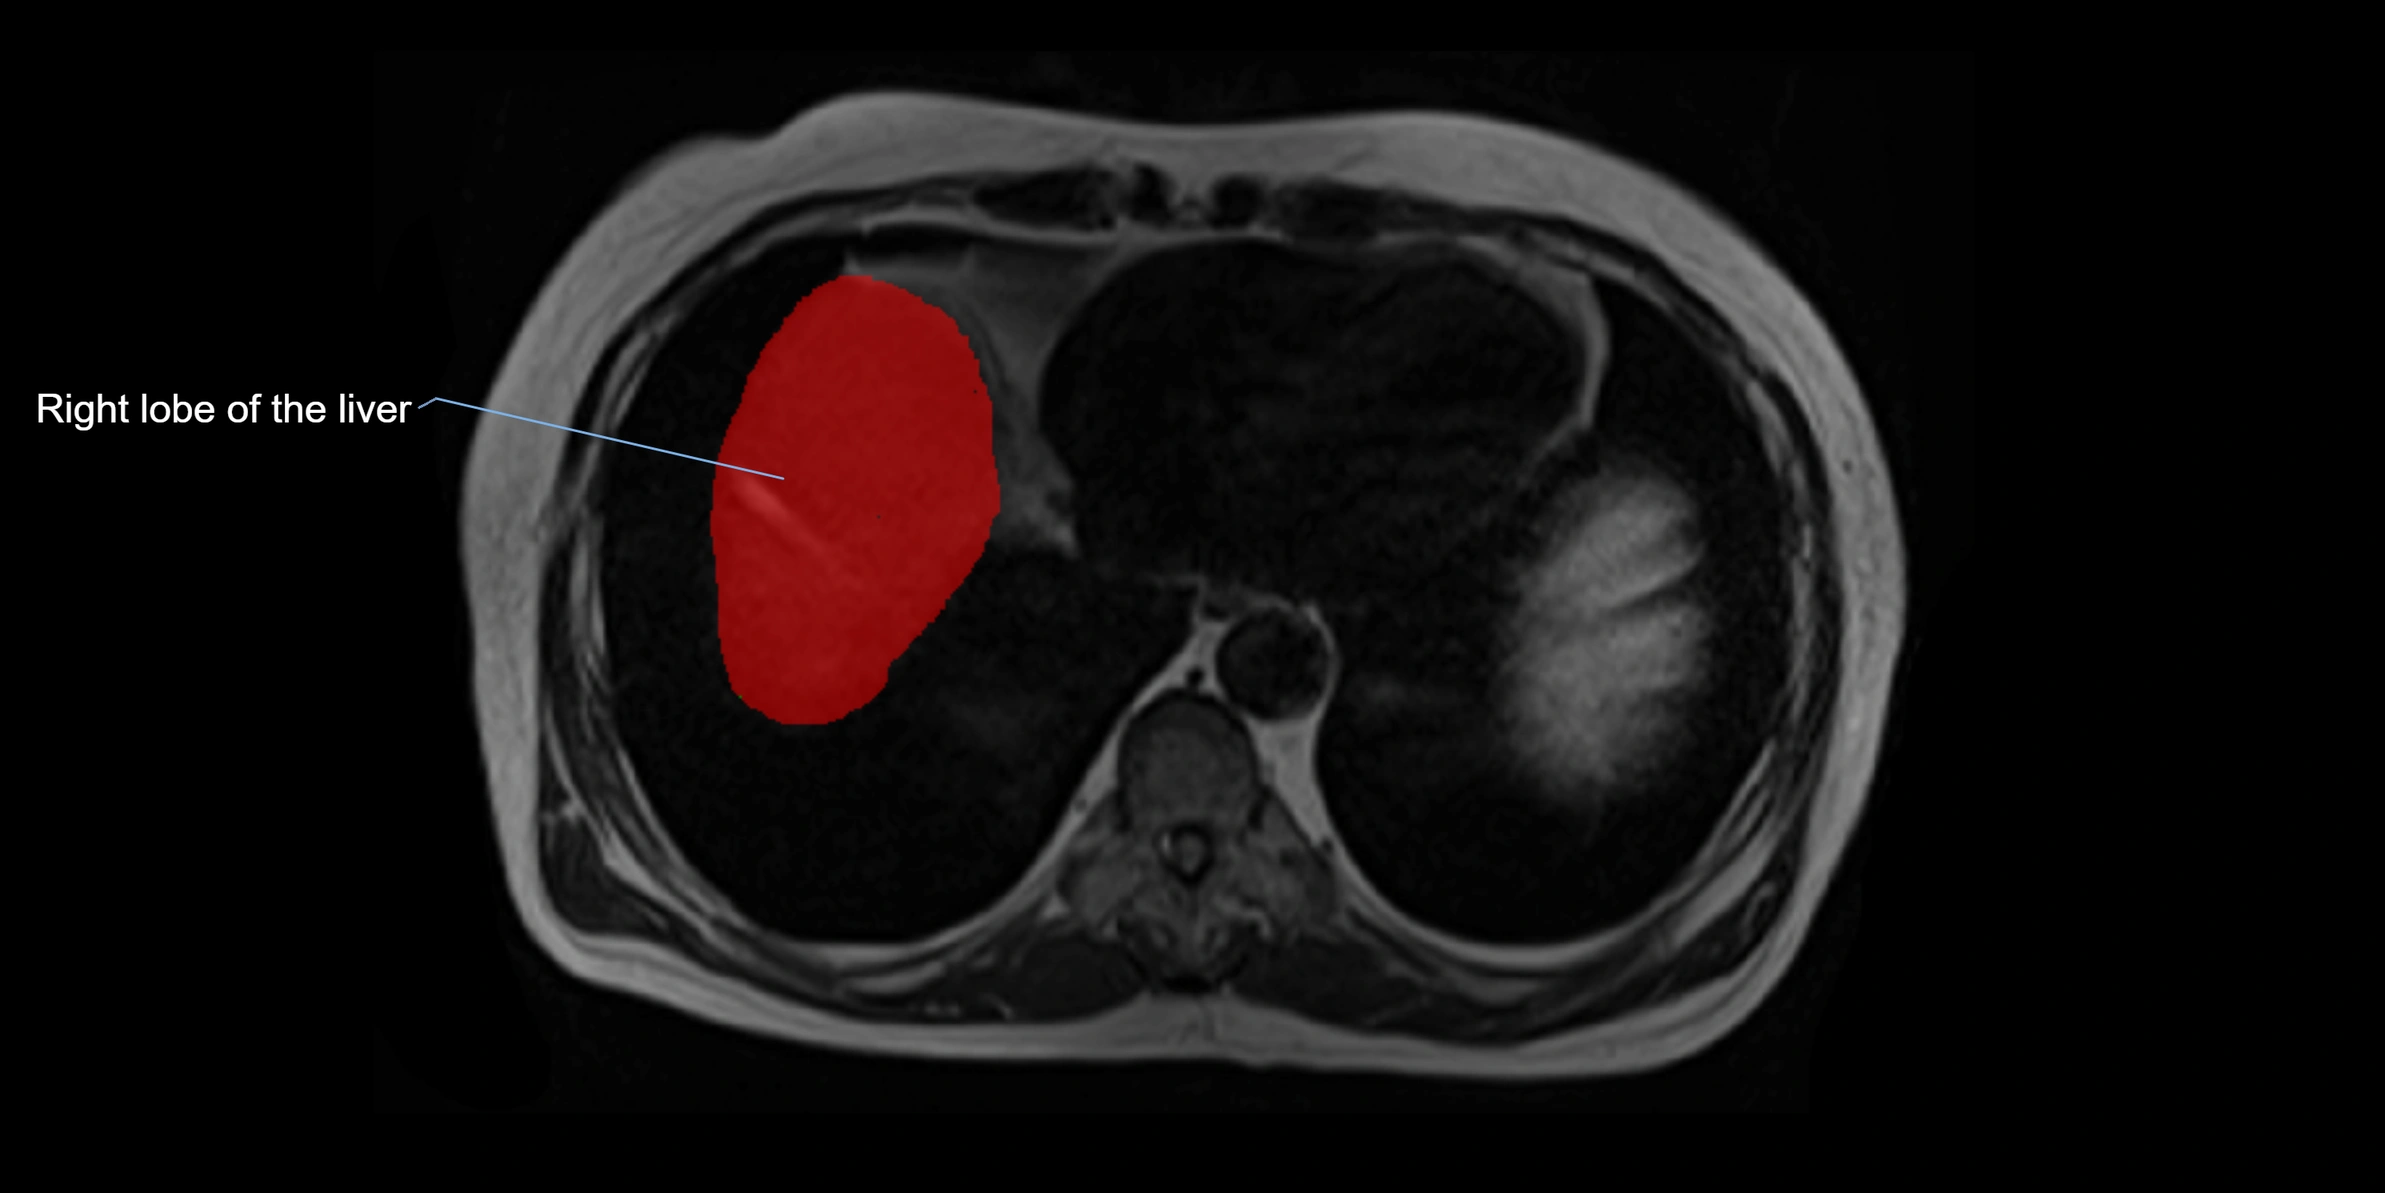

The caudate lobe of the liver is a distinct anatomical subdivision of the liver, designated as segment I in Couinaud’s classification. It lies on the posterior surface of the liver, between the fissure for the ligamentum venosum (left boundary) and the groove for the inferior vena cava (IVC) (right boundary). Superiorly, it is related to the posterior liver surface, and inferiorly it is separated from the left lobe by the porta hepatis.

MRI image

image